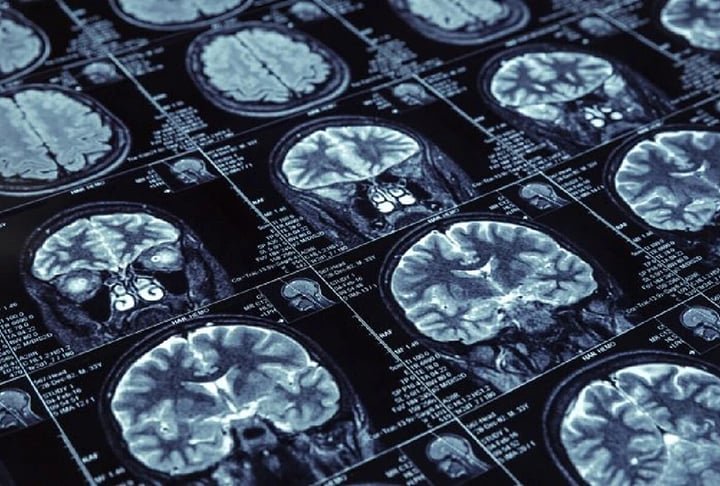

Os exames no jovem identificaram uma atrofia do hipocampo cerebral, além do acúmulo da proteÃna beta. As duas são caracterÃsticas da doença. Também houve um aumento da proteÃna tau, outra caracterÃstica. Foto: Reprodução -

O Mal de Alzheimer é uma doença degenerativa, ou seja, uma doença que vai destruindo o seu corpo e o leva à morte. O Alzheimer não tem cura e, aos poucos, vai comprometendo as funções cerebrais. Foto: - Dominio Publico/freepik -

cérebro Foto: Tânia Rêgo/Agência Brasil -